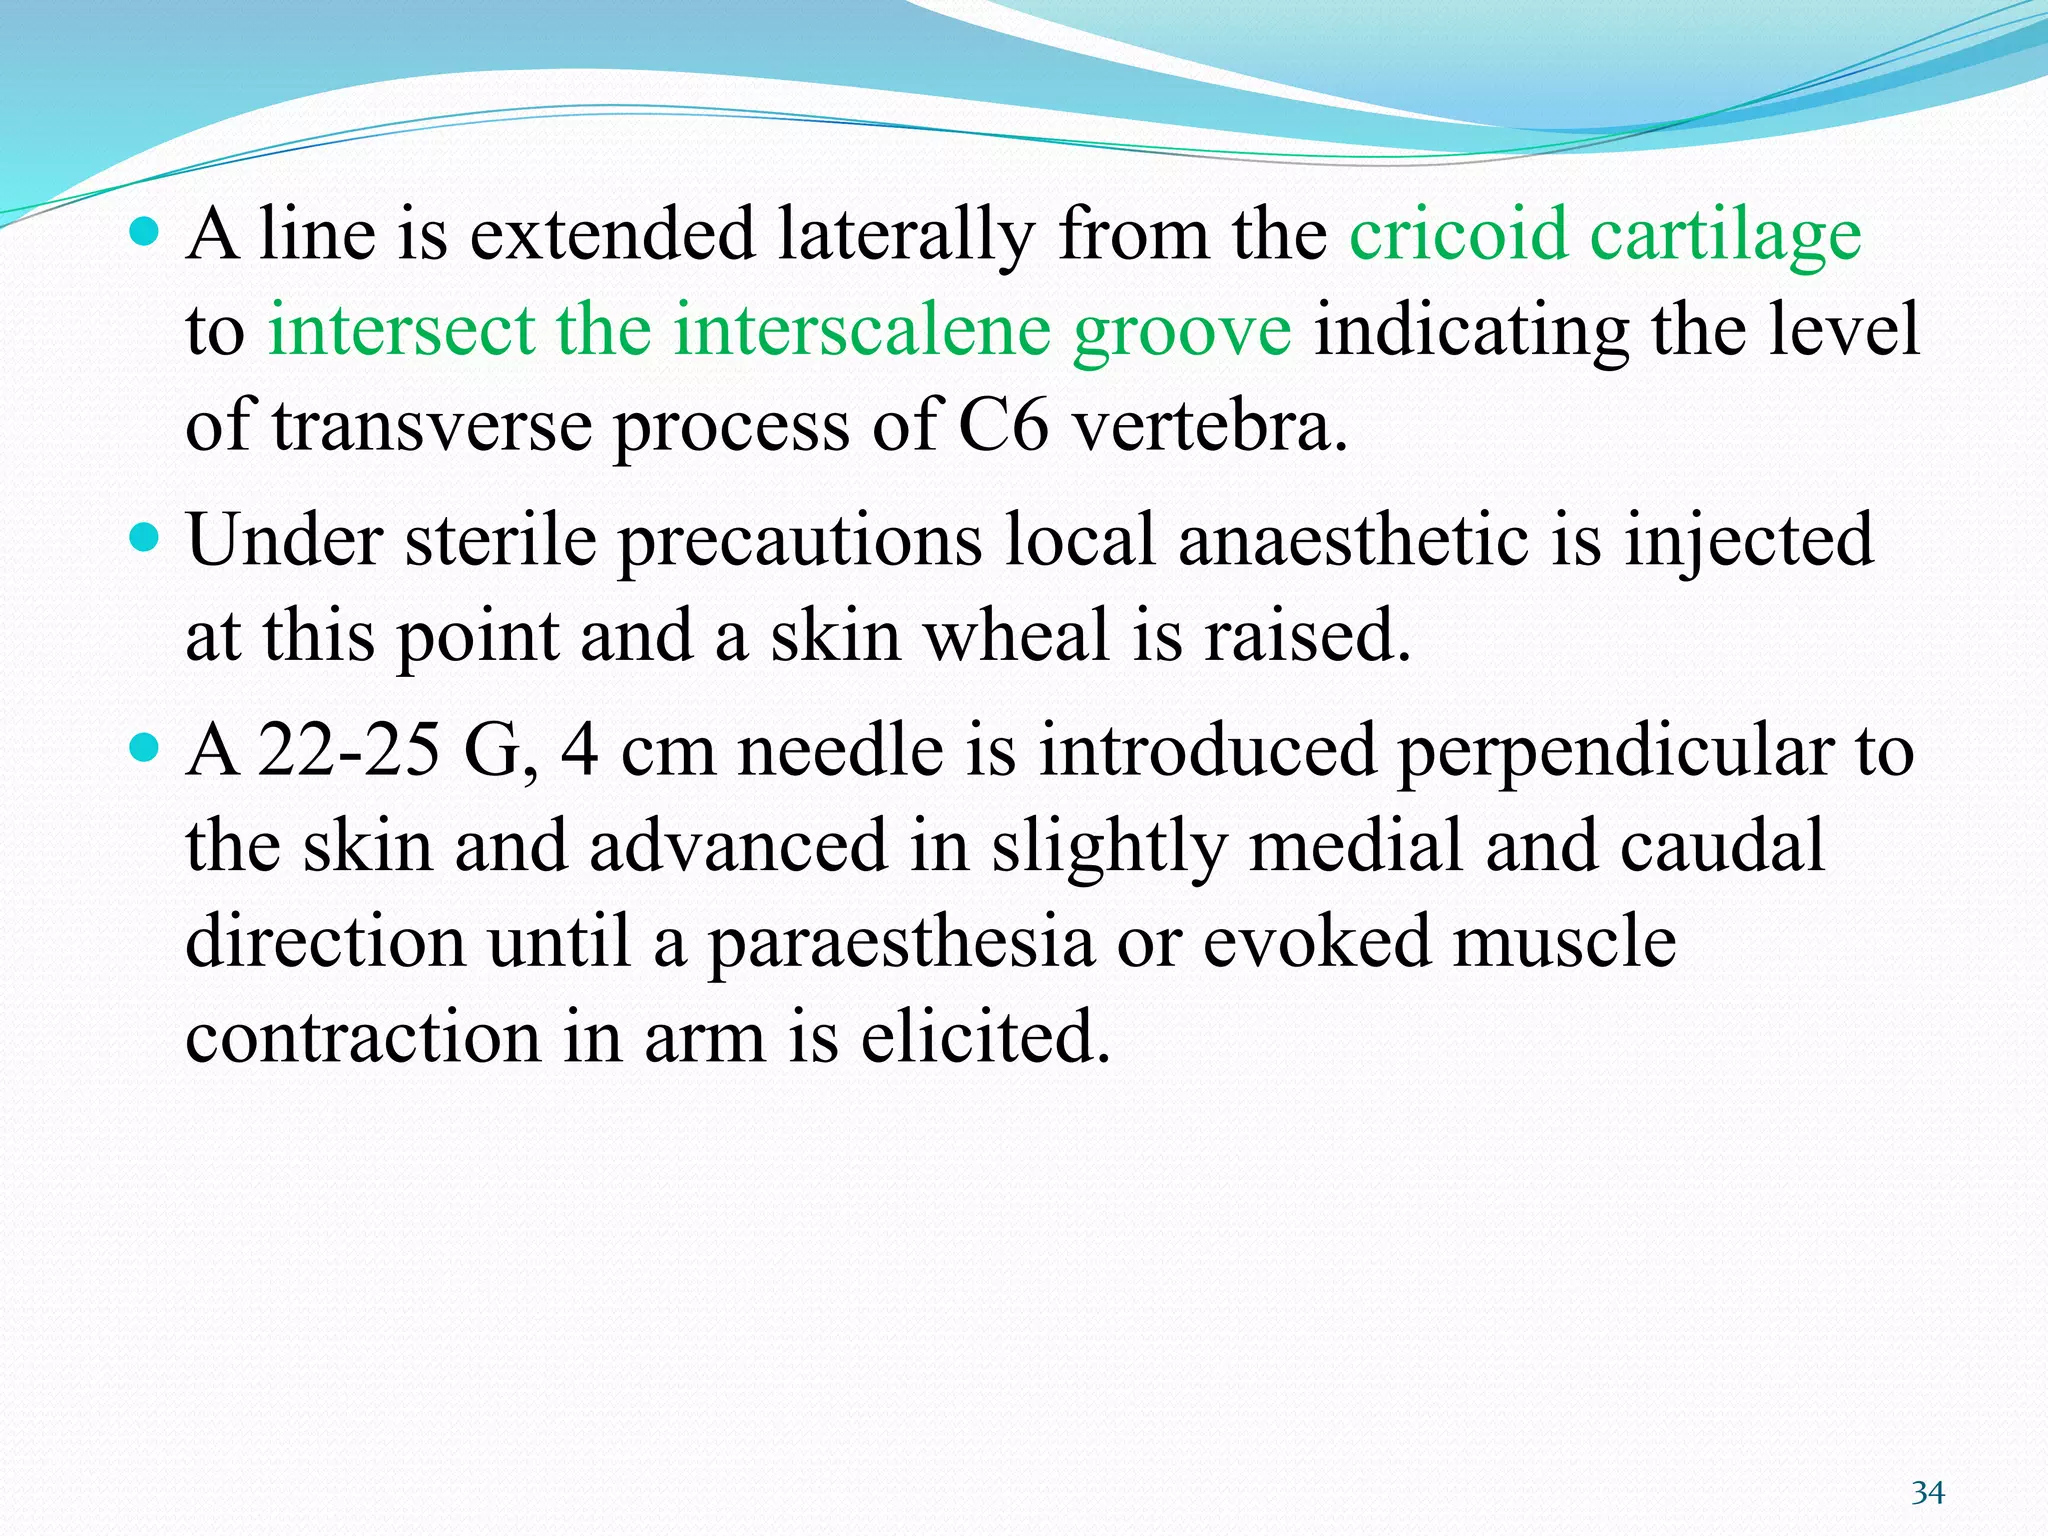

This document provides an overview of brachial plexus anatomy and techniques for brachial plexus nerve blocks. It begins with a description of the brachial plexus formation from cervical and thoracic nerve roots and its branching pattern. Four main approaches for brachial plexus nerve blocks are described: interscalene, supraclavicular, infraclavicular, and axillary. Details are provided on the anatomy and techniques for performing interscalene and supraclavicular brachial plexus blocks. Ultrasound guidance is discussed as an advancement which allows real-time visualization of needle and nerve. Complications are also summarized.